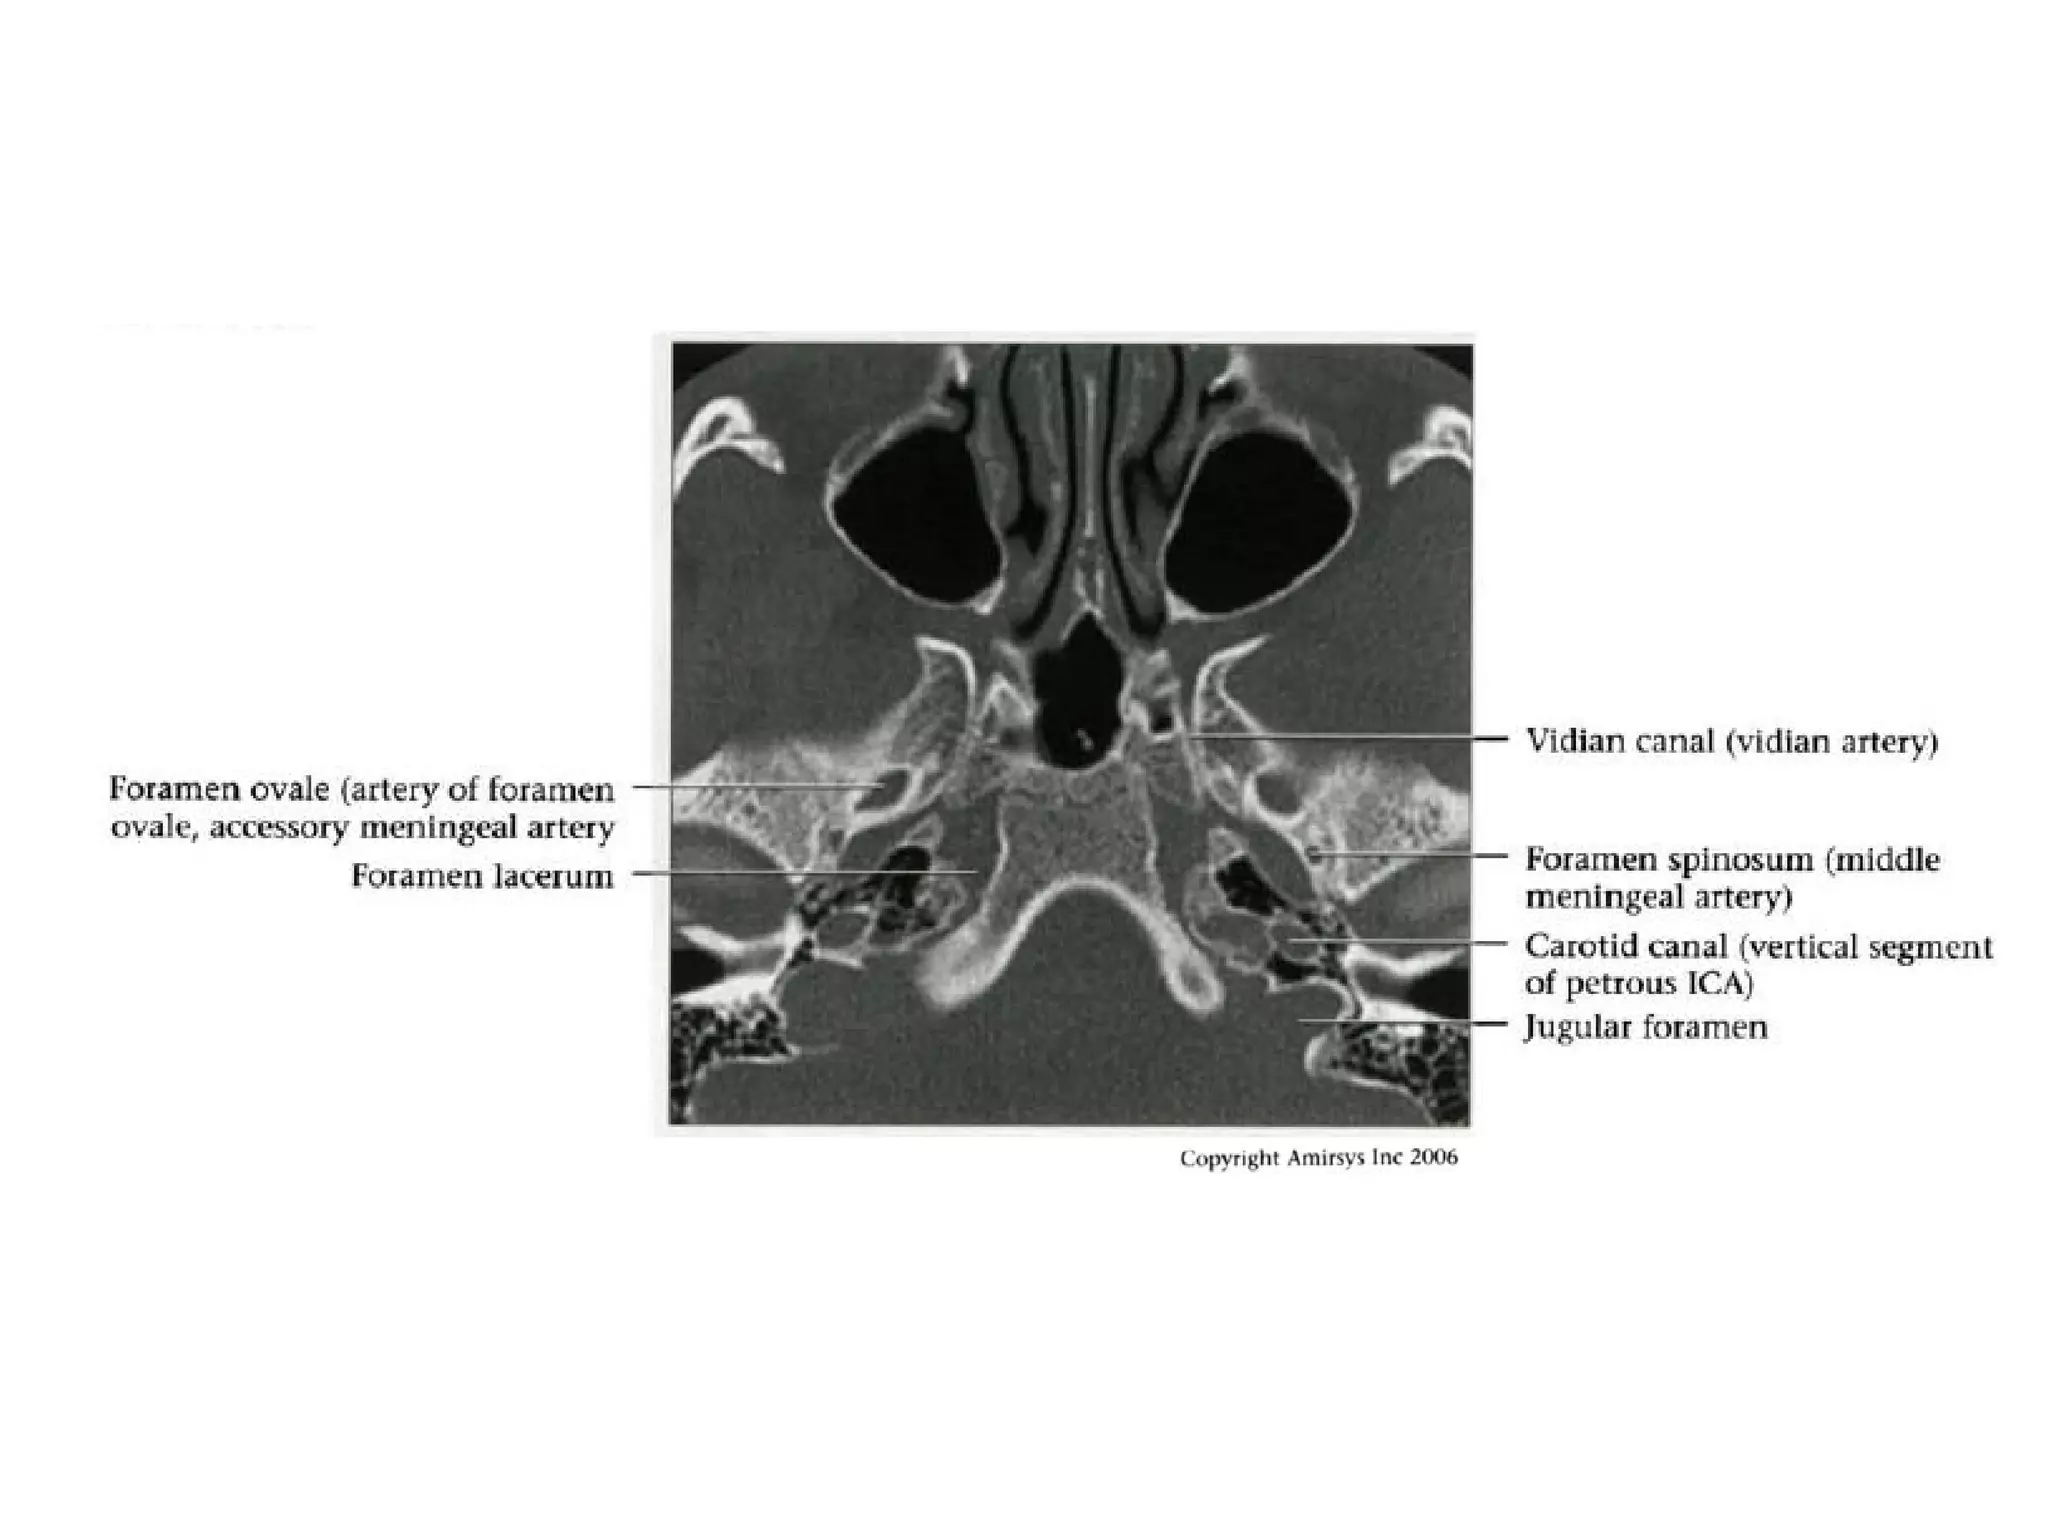

Petrous (C2) segment

• Contained within carotid canal of temporal bone

- Two C2 subsegments joined at genu

• Short vertical segment - anterior to internal jugular vein

(lJV)

• "Genu" (where petrous ICA turns anteromedially in front

of cochlea)

• Longer horizontal segment

- Exits carotid canal at petrous apex

- Branches

• Vidian artery (artery of pterygoid canal)

anastomoses with external carotid artery (ECA)

• Caroticotympanic artery (supplies middle ear)

Lacerum (C3) segment

• Small segment that extends from petrous

apex above foramen lacerum, curving

upwards toward cavernous sinus